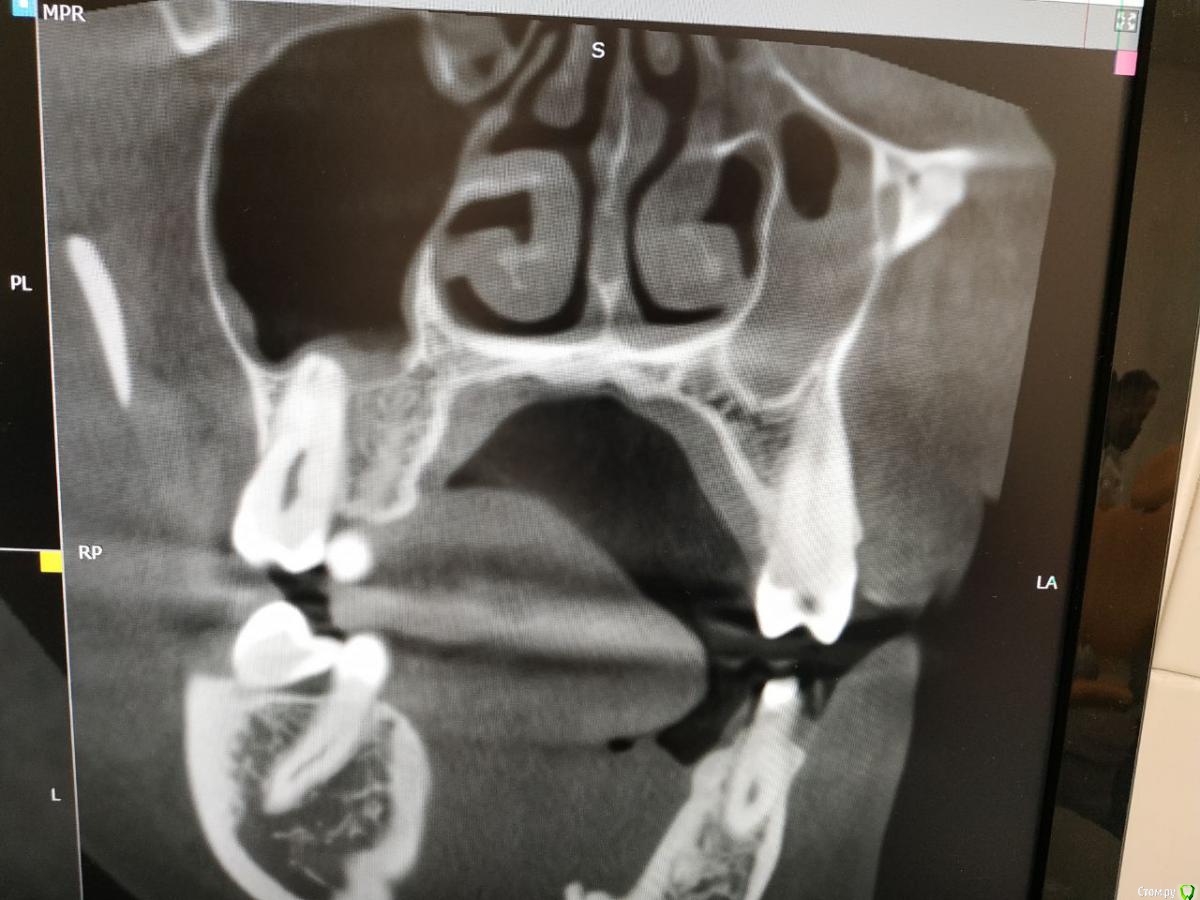

red_butler Опубликовано 4 февраля, 2020 Поделиться Опубликовано 4 февраля, 2020 Покажите ещё срезы Кт Ссылка на комментарий

Liza544 Опубликовано 4 февраля, 2020 Автор Поделиться Опубликовано 4 февраля, 2020 Вот еще пару снимков которые у меня есть. ПРошу заметить, что последние 4 снимка (файлы 7-10), которые я тут прикрепила - до пломбы на 25-м зубе и до залеченного 4-го канала в 26-м зубе. Подскажите пожалуйста, может ли быть зуб недостаточно залечен, хотя на КТ ничего подозрительного не видно? Ссылка на комментарий

ЛанаМ Опубликовано 4 февраля, 2020 Поделиться Опубликовано 4 февраля, 2020 Воспаление десны может давать постоянные ноющие боли и боль при накусывании. От чистки сразу не пройдет, нужно дней 5-7 противоспалительного лечения и отсутствие травмирования (постараться ниткой не чистить). Также нужно убедиться, что нет хронического воспаления в гайморовой пазухе. Побольше срезов кт, желательно уже после пломбирования четвертого канала. Да, бывают проблемы в зубе и при идеальной картинке рентгеновского снимка. На нем видны только крупные каналы, а там еще целая сеть мелких. Ссылка на комментарий